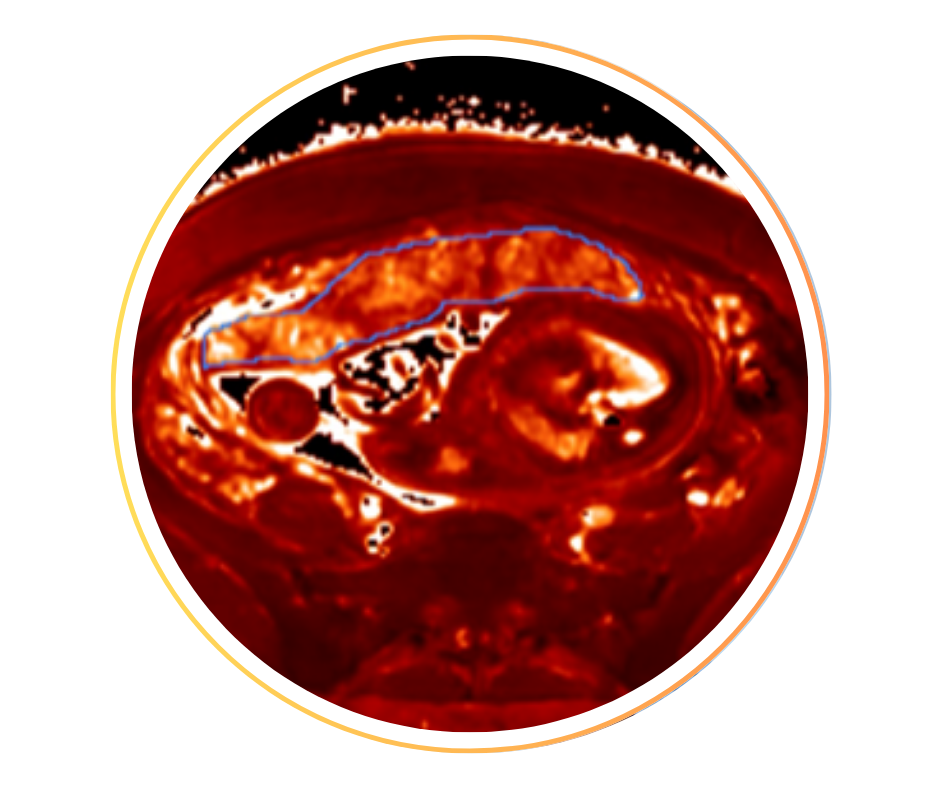

• Cœur fœtal, développement normal et cardiopathies : fusion écho/IRM cardiaque, segmentation, volumétries cardiaques.

• Cerveau fœtal, développement normal et neuro-pathologies : fusion écho/IRM cerveau, perfusion cerveau ASL, tractographie, segmentation, analyse gyration.

• Placenta, fonctionnement normal et pathologies placentaires : fonctionnalité placentaire normale et pathologique, imagerie multimodale (ASL, BOLD, T2*, DCE, …), placenta pathologiques (monochoriales, …).